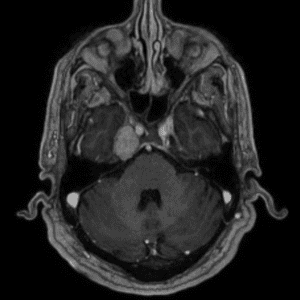

Brain Tumor Practice Cases

Case #5

Neurofibromatosis type II